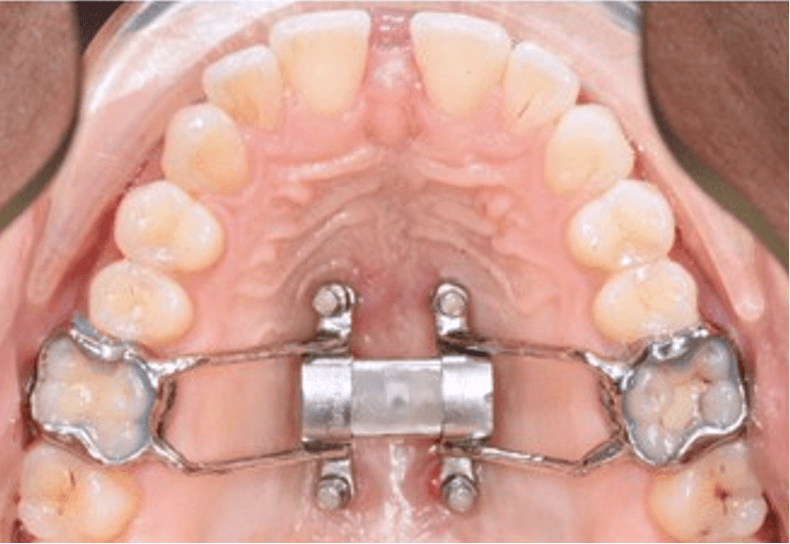

For adults, airway-focused orthodontics may involve braces, aligners, miniscrew-assisted rapid palatal expanders (MARPEs), or surgical treatment to help reduce snoring or sleep apnea. If needed, Dr. Gross can collaborate with ENTs (ear, nose, and throat physicians), sleep specialists, and oral and maxillofacial surgeons to create a comprehensive care plan.